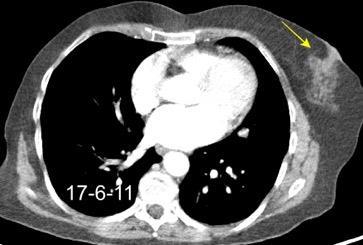

Rehúsa cirugía

2011. Acude por masa axilar

Linfoma NH de cél. B. Invasión Transtorácica.

Afectación axilar